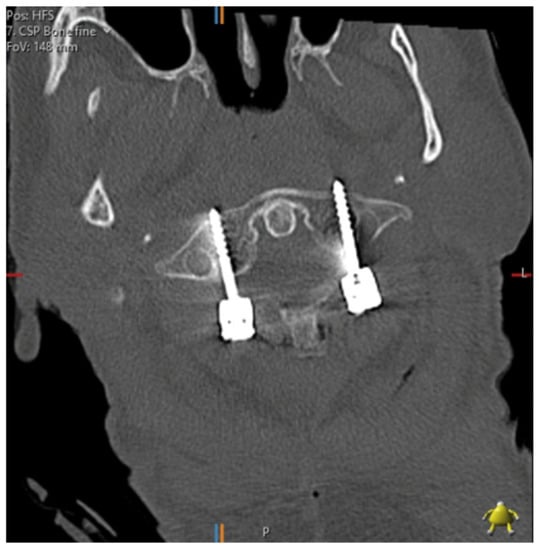

Pedicle screw insertion in the cervical spine is complicated by the smaller pedicle widths, the larger transverse pedicle angles and the proximity of the vertebral arteries, nerve roots and spinal cord. Factors affecting anatomy include gender, age, height and race [6]. Figure 1 shows a post-operative axial CT image of a patient who underwent cervical spine pedicle screw fixation with a fatal injury to the vertebral artery. Several authors have converged on the 4 mm pedicle width as the smallest sized pedicle that would be appropriate for pedicle screws [5,6,22]. The thickness of soft tissues over the posterior neck must also be considered—thick muscle and fat has been suggested to be a greater cause of pedicle wall violation than pedicle diameter [6].

Figure 1. C1/2 fixation performed under fluoroscopic guidance; the left foramen transversarium has been penetrated by a pedicle screw. The patient suffered a massive posterior stroke and died within 24 h.